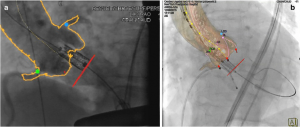

SHDにおけるデバイスの発達とともに、画像診断における役割はより治療に直結するものに変わりつつある。治療前の評価のみならず、治療中のガイドに関してもX線透視とのfusion技術などが用いられ始めている(14)。

(文献14より引用: TAVR術中のfusion imaging)

(文献14より引用: TAVR術中のfusion imaging)